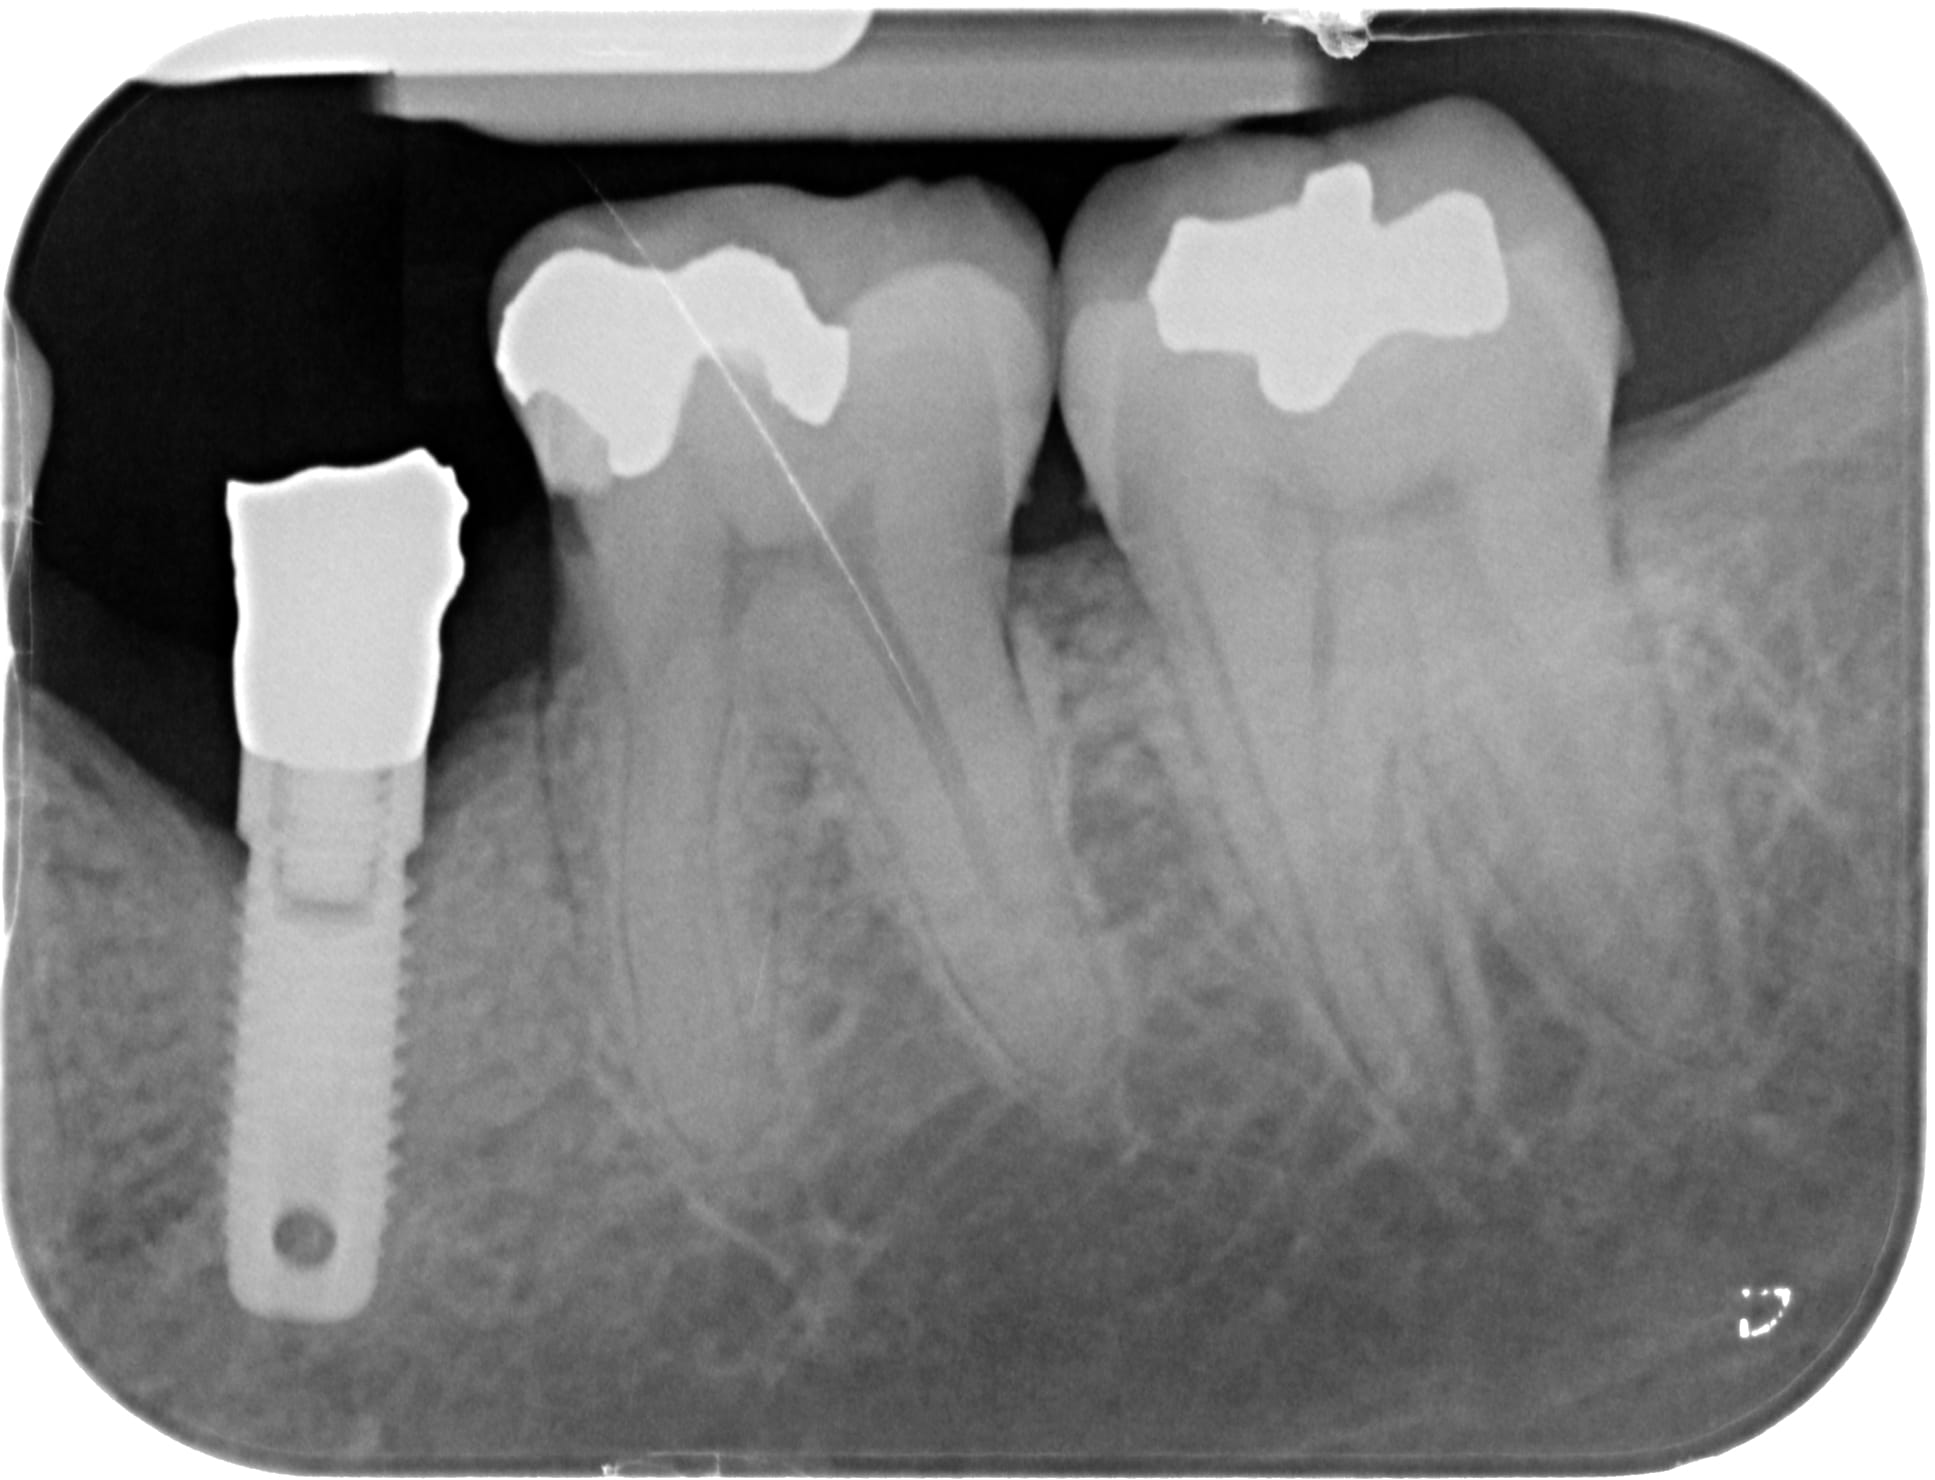

Bonjour à tous, qui peut me dire de quelle marque sont les différents implants de cette radio ?

oui désolé... c'est mieux? plutôt Nobel la 35 non ?

première radio: Sterioss

les 2 autres photos (du même implant)....çà ressemble à du MIS Lance ou similaire....pour moi la connexion doit être un standard "Zimmer"....